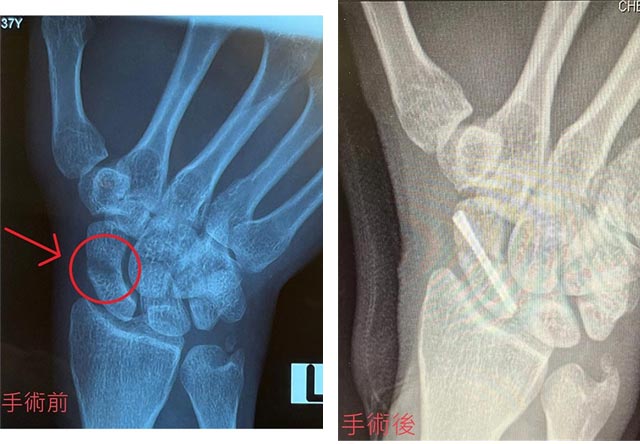

病人打籃球時不小心雙掌撐落地下,之後持續手腕疼痛。在X光及磁力共振檢查下確定為舟骨骨折。

微創手術以螺絲將舟骨骨折固定

較理想的處理方法是以微創手術以螺絲將舟骨骨折的位置固定,不需額外打石膏,而螺絲亦不用再取出,術後只需要暫停6星期的劇烈運動,日常生活不受影響。